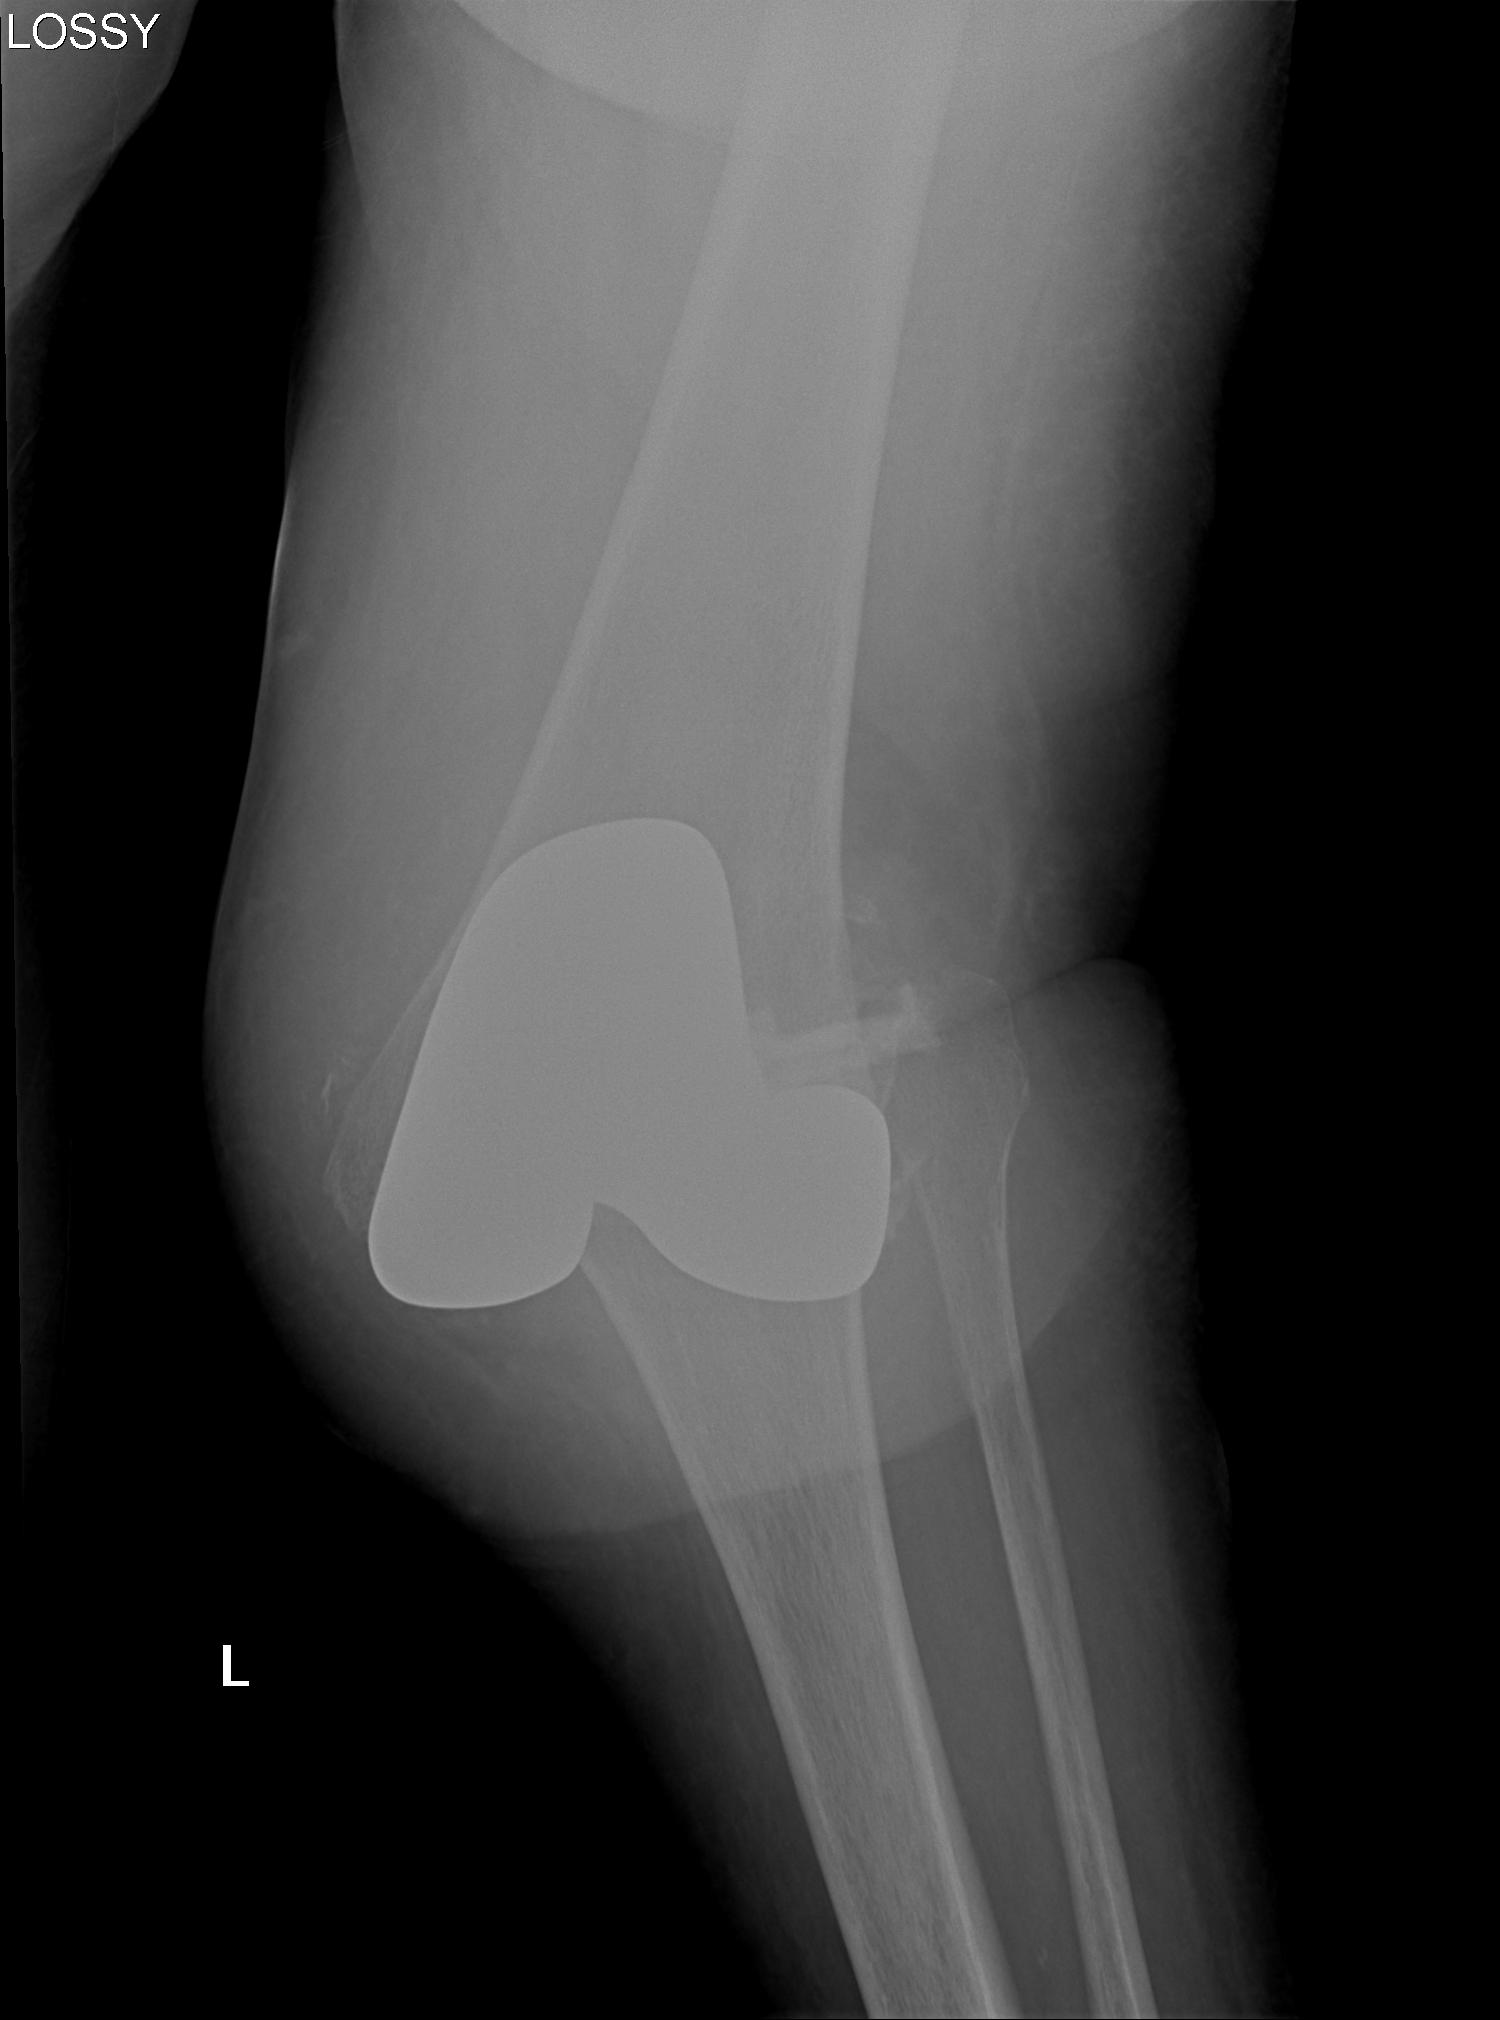

1. AP Instability

2. Varus Valgus Instability

3. Global Instability

4. Frank Dislocation